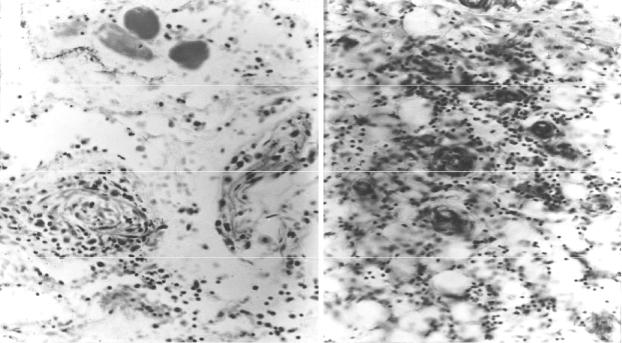

Рис. 28. Клостридиальная анаэробная раневая инфекция, вызванная

Clostridium perfringens (окраска по Граму а, б, в, д, азуром II-эозином г): а

анаэробный миозит с некрозом мышечных волокон на удалении от края раны. В отечном эндомизии крупные грамположительные палочки (клостридии) (× 300); б газовый пузырь среди скопления клостридий в некротизированной мышечной ткани (× 75); в анаэробный целлюлит с наличием клостридий в глубине некротизированной жировой клетчатки (× 500); г некроз и демарка- ционная лейкоцитарная инфильтрация в крае раны (× 250); д полиморфная грамположительная и грамотрицательная (бледно окрашенная) микробная флора среди некротического детрита в мазке-отпечатке с поверхности раны (× 1000)

Неклостридиальная пептострептококковая (стрептококковая) ана-

эробная гангрена по клинико-морфологическим проявлениям весьма близка к классической клостридиальной анаэробной гангрене. Чаще она принимает форму преимущественно серозно-гнойной некротической (гангренозной) флег- моны жировой клетчатки (анаэробный целлюлит) или распространяется пре- имущественно по фасциям (анаэробный фасциит). В подлежащих к очагам нек- роза тканях можно обнаружить перифокальный тромбоваскулит (рис. 29). По- следний развивается вне непосредственной связи со скоплениями микробов- возбудителей и может служить видом гиперергической реакции, разные прояв- ления которой характерны и для обычной гнойной стрептококковой инфекции.

Рис. 29. Стрептококковая анаэробная инфекция в огнестрельной ране бедра, 7-е сутки после ранения (окраска азуром II и эозином, × 150): а некроз мягких тканей в месте инвазии возбудителей на удалении 20 см от раневого ка- нала, серозно-лейкоцитарный инфильтрат; б некротический тромбоваскулит

в подлежащей жировой клетчатке